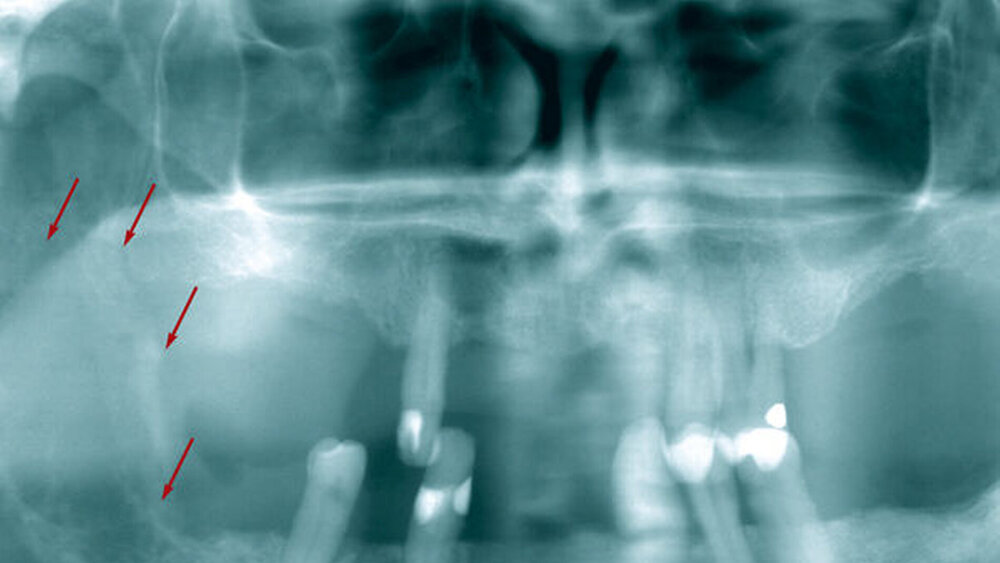

Das angefertigte Orthopantomogramm zeigte eine osteolytische Raumforderung im Bereich des rechten Unterkiefers (Abbildung 1).

Unscharfe Osteolysen in Röntgenaufnahmen können Hinweise auf Tumoren geben.